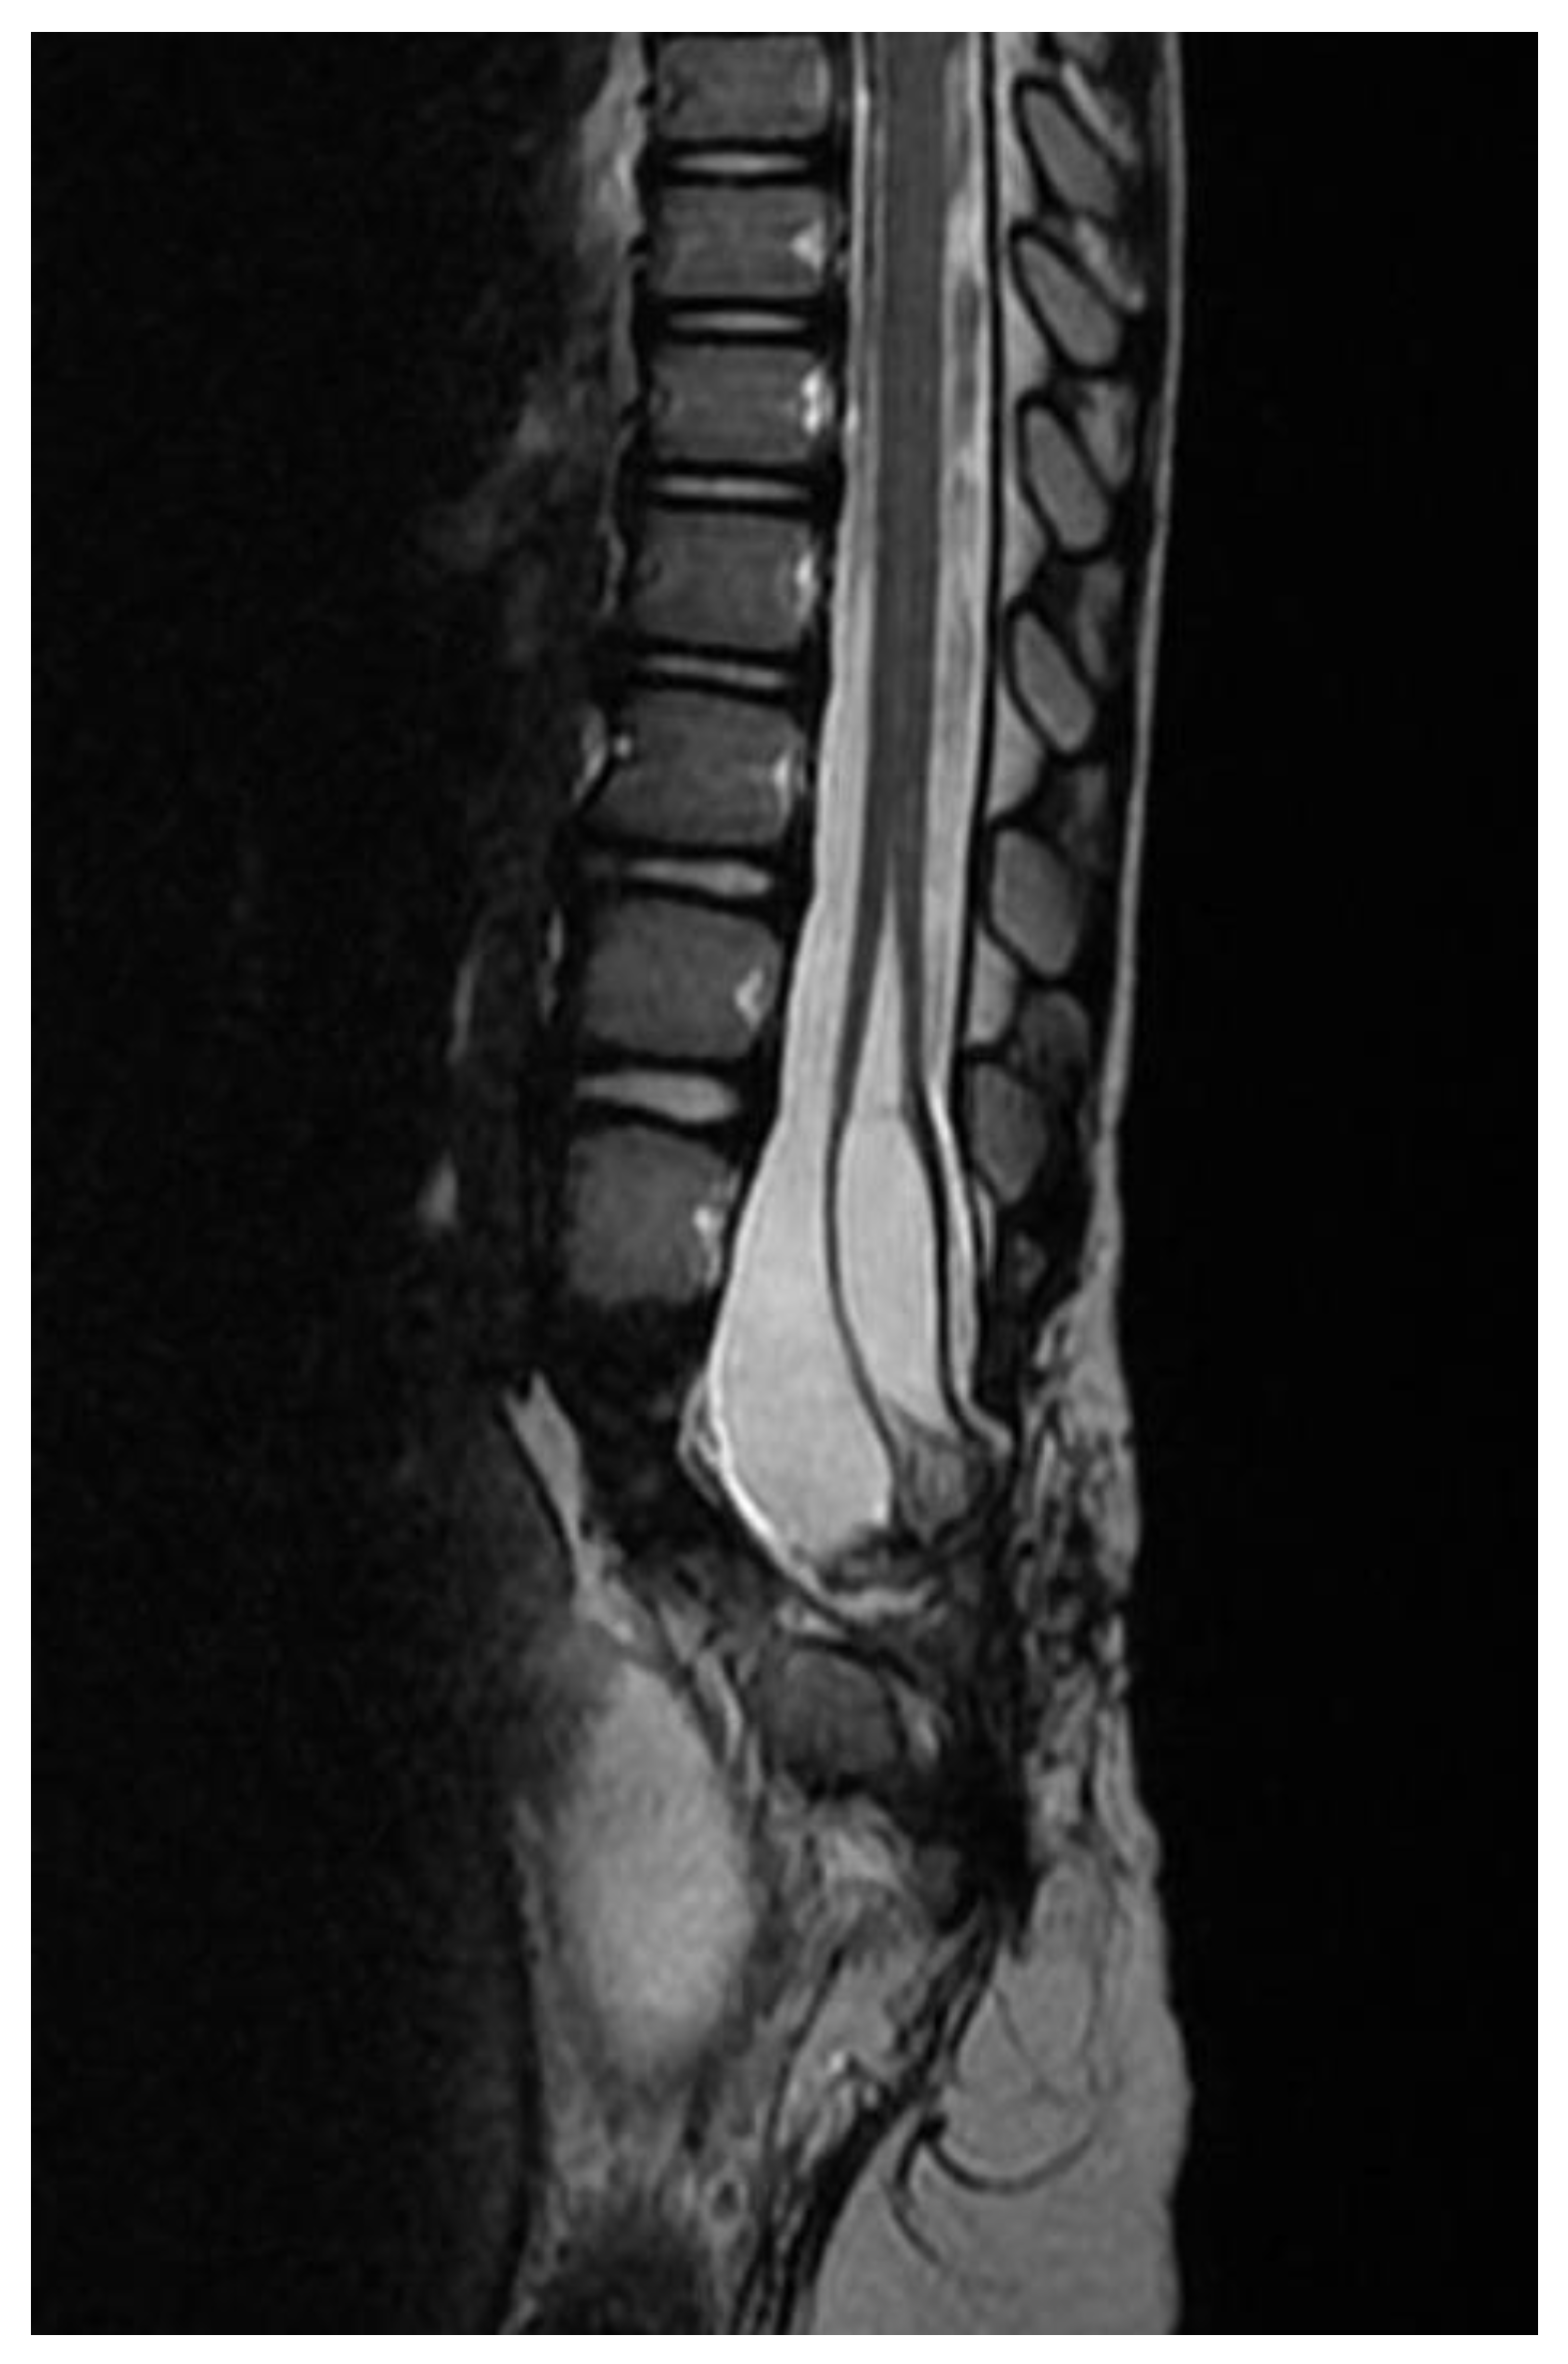

2. Clinical Presentation